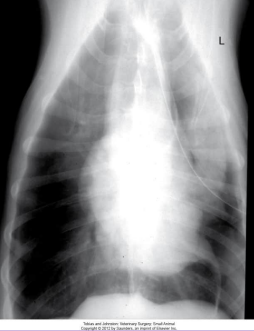

Diaphragmatic Hernia

Et: trauma, pressure gradient disruption, genetic

abdominal organs migrate into thorax, liver is #1

Peritoneopericardial d. hernia (PPDH) → congenital

Sig: Cocker spaniel, Weimaraner, Himalayan, DLH

Cs: shock(acute), dyspnea(chronic), exercise intolerance, ADR

Congenital is asymptomatic

Tears → weakest areas: muscle

Dt: thoracic rads (#1), US, CT

Tx: Sx (8-16w if congenital) (trauma: be ready for anything)

abdominal explore, identify hernia, reduce contents, close defect (absorbable 3-0 PDS, simple continuous, dorsal → ventral), remove air

Caution of adhesions

Do not close the pericardial sac (genetic)

Risk: re-expansion pulmonary edema, abdominal compartment syndrome, ARDS

Do NOT manually re-expand lungs, do not close pericardial sac